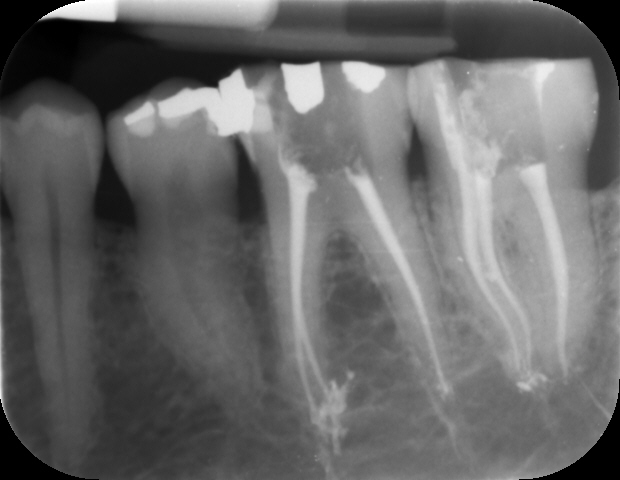

RADIOLOGIA DIGITALE

Negli ultimi anni la Radiologia Digitale sta sostituendo integralmente la Radiologia tradizionale.Il più moderno sistema digitale di acquisizione dati consente di visualizzare direttamente l’immagine radiografica sul monitor di un computer, ottimizzando, a beneficio del paziente, l’operato dell’ odontoatra. Il nostro studio utilizza la radiologia digitale da oltre 20 anni con piena soddisfazione nostra e dei nostri pazienti.